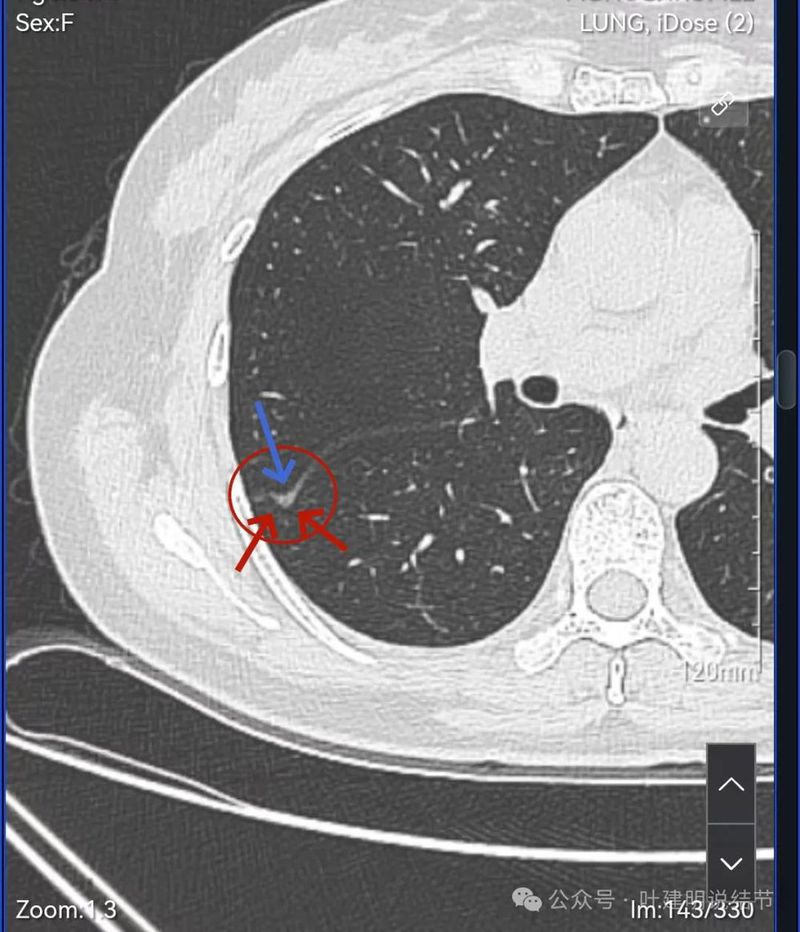

密度不太纯,轮廓与边界清。

表面分叶,中间空泡,边缘有磨玻璃成分,叶间胸膜凹陷。